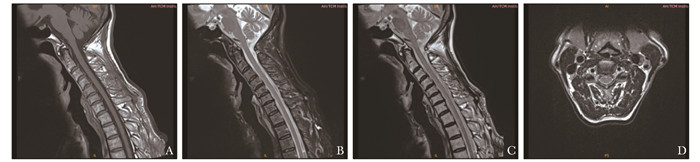

自身免疫性胶质纤维酸性蛋白星形胶质细胞病临床特征分析

郑秀君, 林麒, 舒崖清, 孙晓渤, 钟晓南, 李蕊, 常艳宇, 邱伟, 王玉鸽

2022, 1(2): 137-141. DOI: 10.12376/j.issn.2097-0501.2022.02.007

摘要 HTML全文 PDF